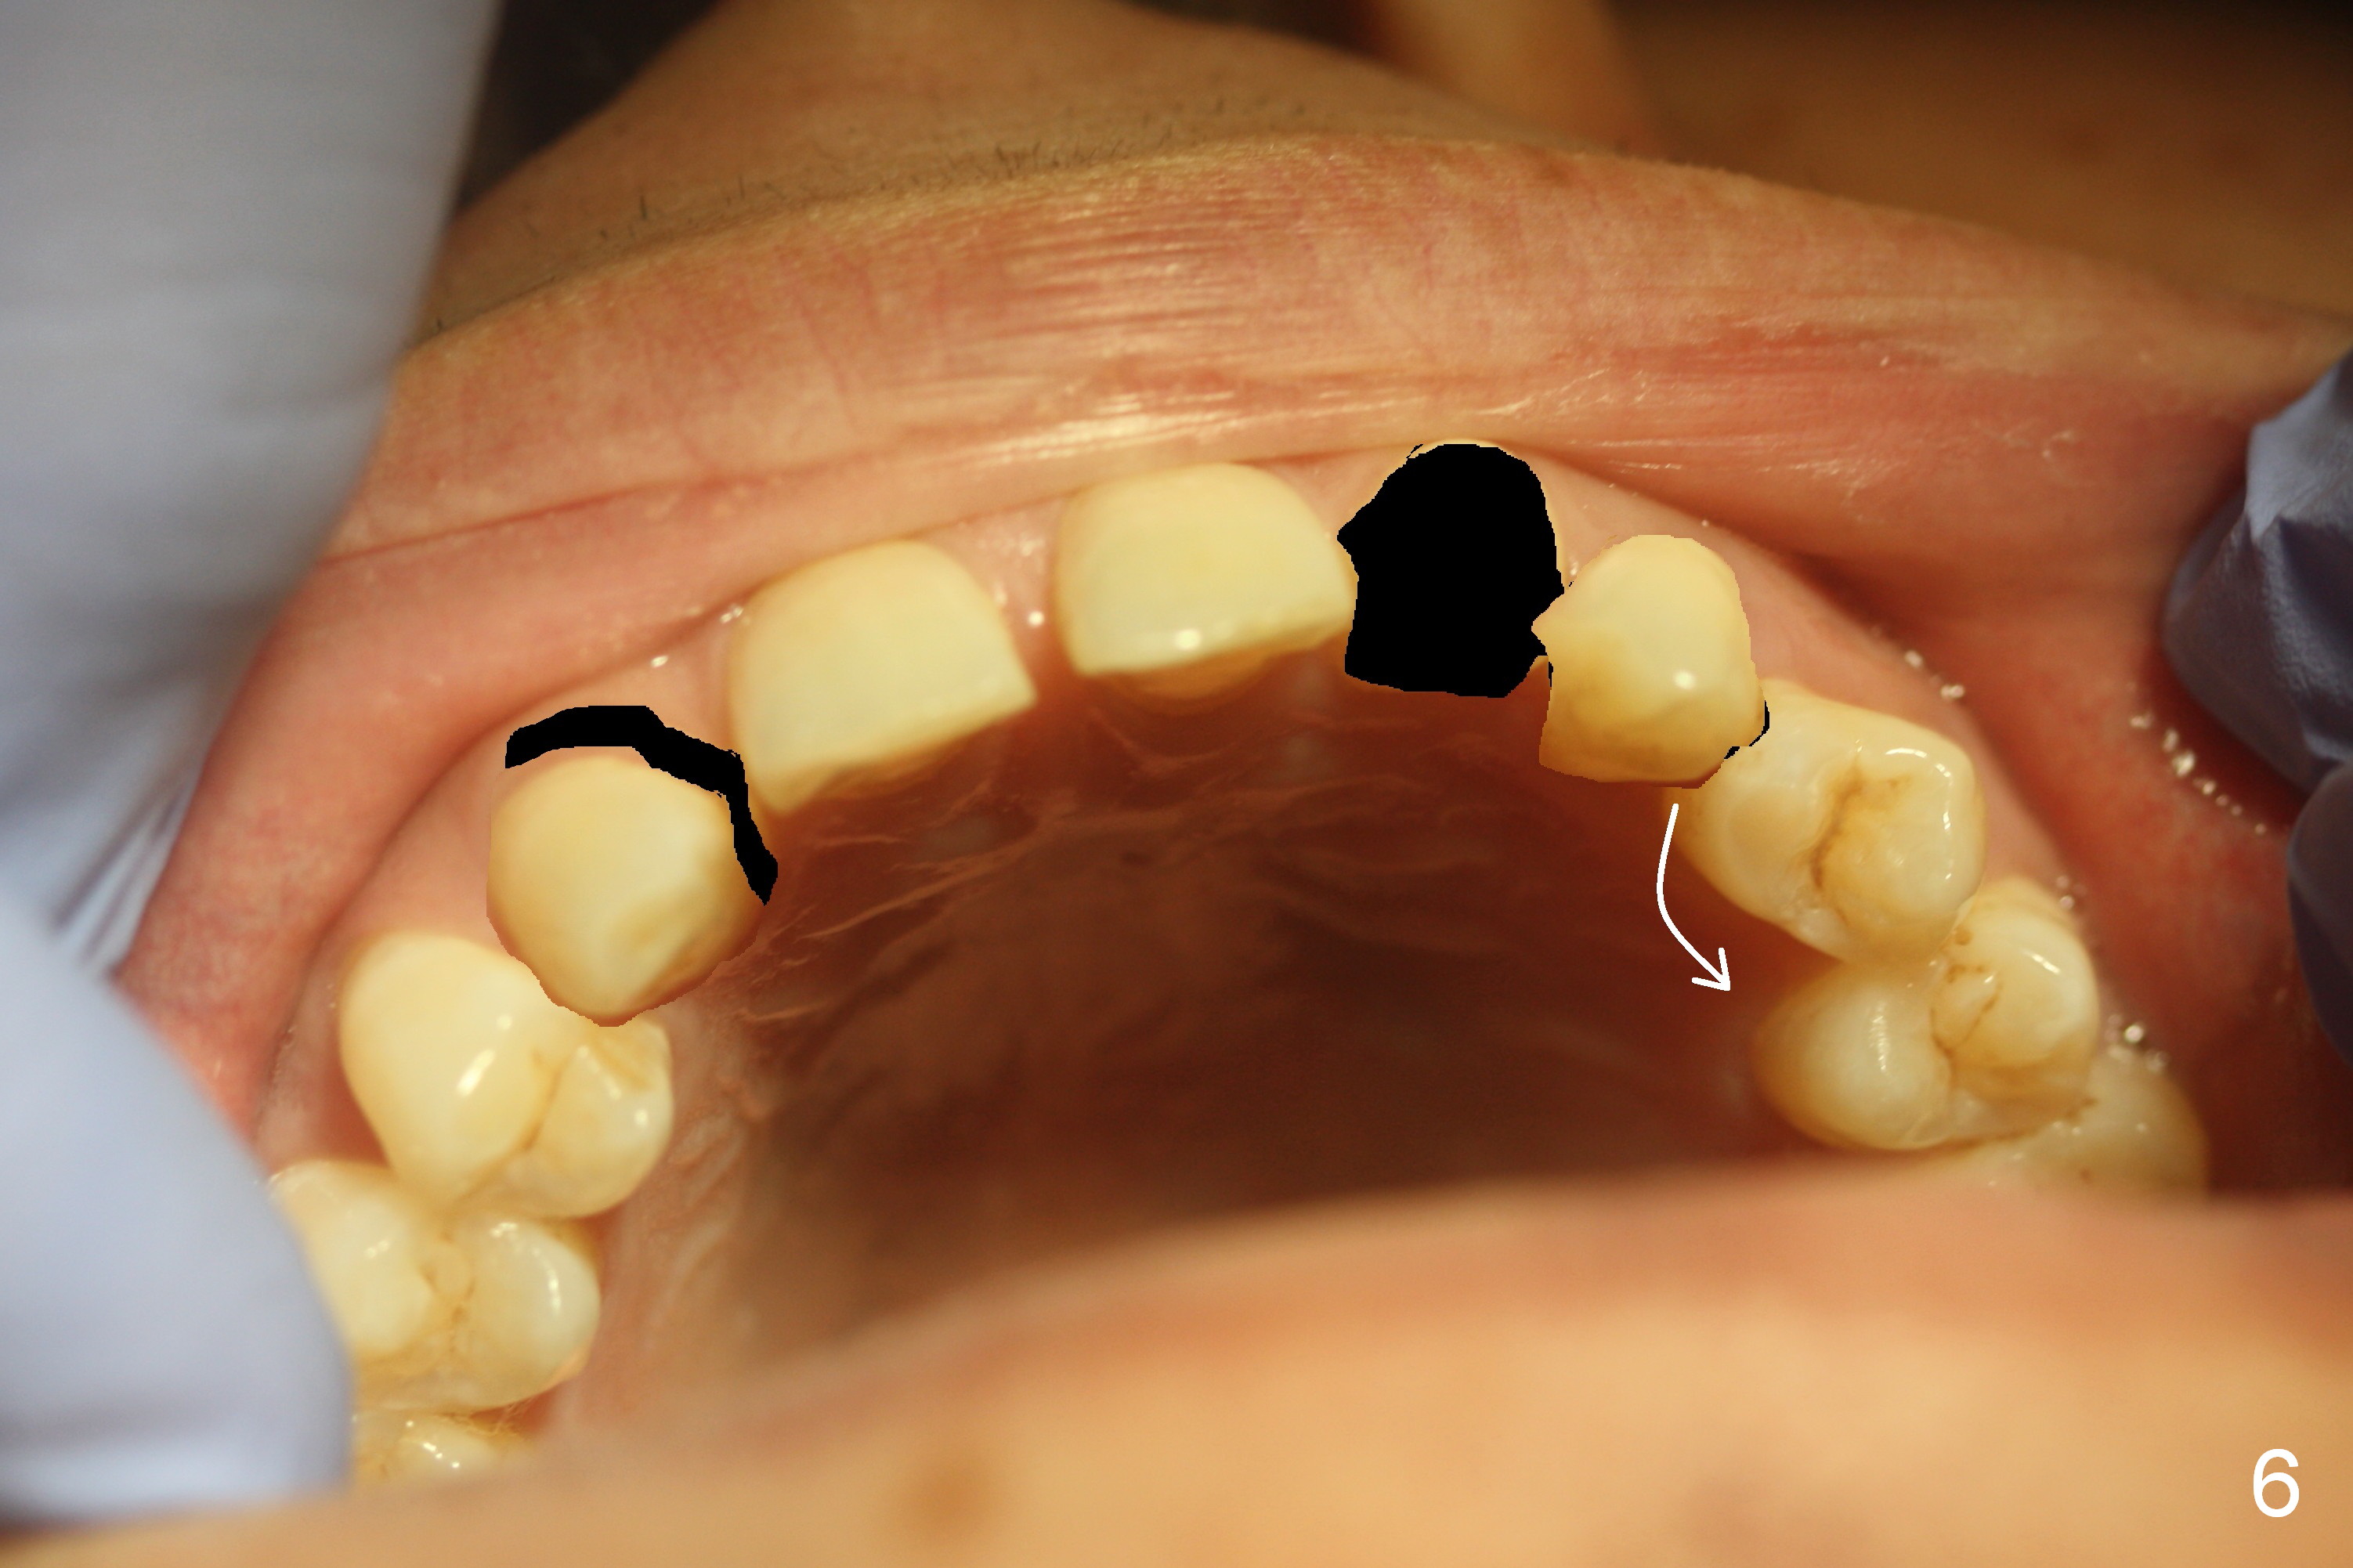

A 38-year-old man has congenitally missing laterals (Fig.1,2) with retention of a deciduous canine (Fig.2,3 C). UL 4 (upper left 1st bicuspid) rotates (Fig.3). LR7 has been extracted (Fig.4).

To improve cosmetics, extract the deciduous tooth (Fig.5), place brackets for the maxillary teeth (6-6), including a lingual button on UL4 to correct the rotation and distalize U3s (Fig.6), close the upper midline diastema and change the midline if needed (Fig.7) and finally place small-diameter implants at U2s (Fig.8 white circles).